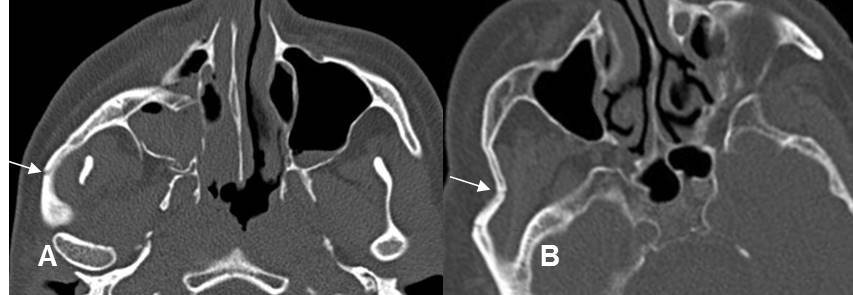

Fig 214. Fractura del arco cigomático.

A y B: TAC axial. Fracturas del arco cigomático. Lineal en A y deprimida en B.

En ambos casos hay otras fracturas asociadas de los antros maxilares.